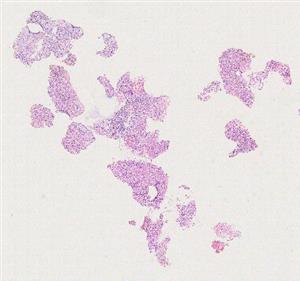

10517 |

左乳肿块 |

女, 52岁, 体检发现乳房结节,已婚已育,已绝经,否认家族遗传病史。否认家... |

上海市第一人民医院 |

有诊断 |